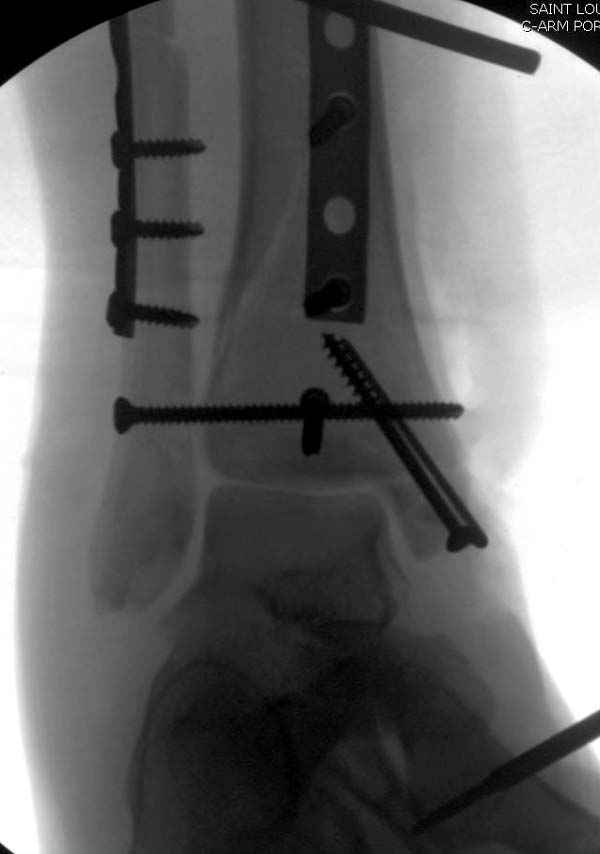

По снимкам довольно сохранный сустав, и такой сустав желательно попытаться восстановить всеми возможными мерами.

Насчет пилона, прошло достаточное время для консолидации и прекрасная возможность для демонстрации, что такие случаи могут быть успешно вылечены остеотомией, несмотря на засторелость.

Из заднего доступа остеотомия тонким остеотомом и коррекции на ЭОПе.

Без применения сложной конструкции, а обычными параллельными шурупами. Шурупы в 3.5 мм и дополнительно фиксация крючковидной пластиной, сделанной из 3.5 mm semitubular пластиной, Butress или аntiglade фиксация.

Здесь алгоритм фиксации свежего перелома и преоперационный план для обсуждаемого случая.